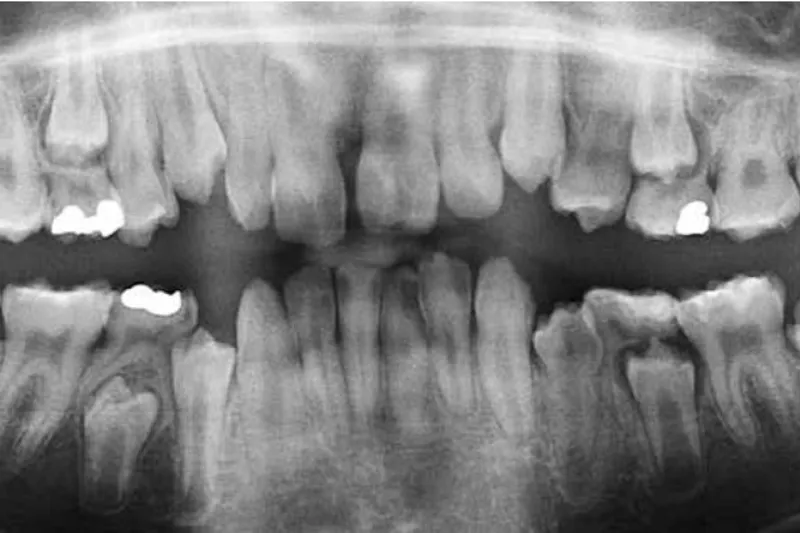

Dysplasi af dentale væv kan optræde som delsymptom ved sjældne medfødte sygdomme. Oversigtsartiklen beskriver udvalgte eksempler på sjældne, medfødte sygdomme, hvor der optræder dysplasi af dentale væv. Emaljedysplasi optræder ved hudsygdommene epidermolysis bullosa (EB) og fokal dermal hypoplasi (FDH). EB, junctional type, har hypomineraliseret og hypoplastisk emalje. FDH har hypoplastisk emalje med uregelmæssig overflade og atypisk kronemorfologi. Begge tilstande medfører store pædodontiske og protetiske behandlingsbehov. Dentindysplasi optræder ved skeletsygdommene osteogenesis imperfecta (OI), der skyldes en kollagen defekt, og X-bunden hypofosfatæmi (XLH), der er en metabolisk knoglesygdom. Dentindysplasi ved OI benævnes dentinogenesis imperfecta (DI) og ses ved svær OI. DI medfører øget risiko for tandfrakturer og tandtab. Ved XLH optræder uregelmæssigheder i hele pulpa-dentin-organet, og der er risiko for spontan udvikling af pulpanekrose. Ved XLH kan også ses elementer af emaljedysplasi (enamel cracks). Cementdysplasi ses ved skeletsygdommen hypofosfatasi (HPP), der optræder i flere alvorlighedsgrader. I varierende grad er tandrodens cementlag acellulær. Der ses præmatur eksfoliering af primære tænder eller ikkeparodontitis-betinget tandtab hos voksne. Svær HPP kan også være associeret med emaljedysplasi.

Dysplasia of dental tissue may appear as a symptom in rare congenital diseases. The present article describes selected examples of rare, congenital diseases in which dysplasia of dental tissues may occur. Dysplasia of enamel occurs in certain diseases of the skin: epidermolysis bullosa (EB) and focal dermal hypoplasia (FDH). EB, Junctional type, has hypomineralised and hypoplastic enamel. FDH has hypoplastic enamel with an irregular surface and an atypical crown morphology. Both conditions entail major pedodontic and prosthodontic treatment needs. Dysplasia of dentine occurs in certain diseases of the skeleton: osteogenesis imperfecta (OI), which is caused by a collagen defect, and X-linked hypophosphatemia (XLH), which is a metabolic bone disease. In OI, the dental symptom is dentinogenesis imperfecta (DI), which mainly occurs in severe OI. DI leads to an increased risk of tooth fractures and tooth loss. In XLH, irregularities occur in the entire pulp-dentineorgan, and the patients experience a risk of spontaneously evolving necrosis of the pulp. In XLH, elements of enamel dysplasia (enamel cracks) may also be present. Dysplasia of the cementum occurs in another disease of the skeleton: hypophosphatasia (HPP). According to degree of severity, HPP is divided into 6 subtypes. To varying degrees, the cemental layer of the root is acellular. Premature exfoliation of primary teeth may occur. In adults, tooth loss not related to periodontitis may occur. Severe HPP may also be associated with enamel dysplasia.